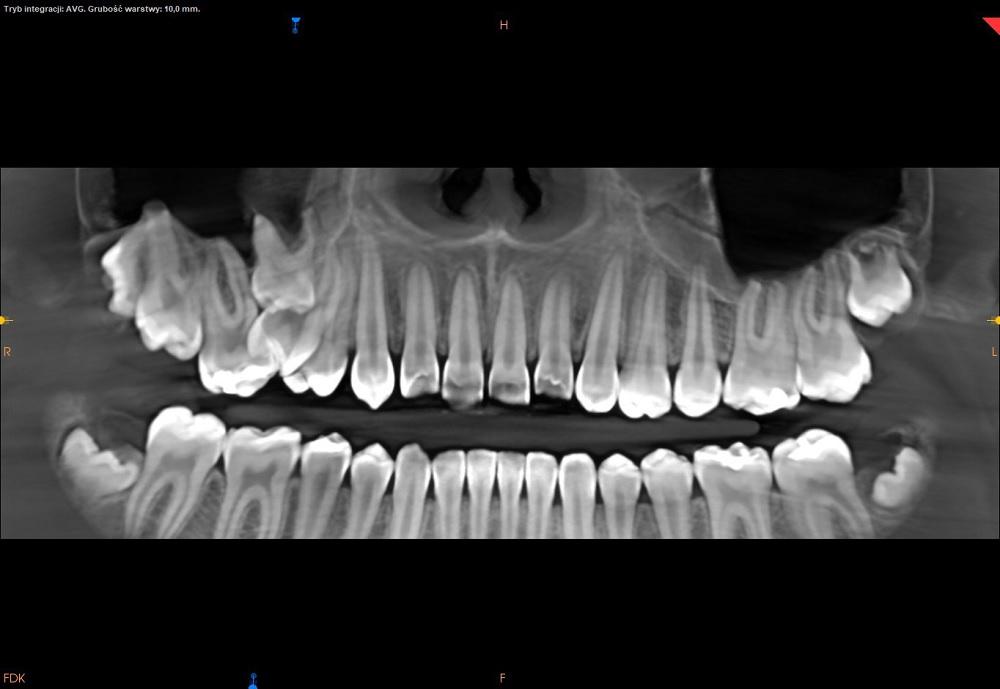

CBCT szczęki.

Badanie tomografii stożkowej (CBCT) uwidoczniło reinkluzję zęba 55 powodującą zaburzenia wyrzynania zębów stałych.

Na ząb reinkludowany wskazano ząb trzonowy mleczny 55 ze względu na położenie, budowę zęba oraz obraz korzenia policzkowego

przedniego, wskazujący na częściową resorpcję.

Ząb reinkludowany bywa również określany mianem zęba zatopionego lub zagłębionego ponieważ isotą zaburzenia jest odsuwanie się od

płaszczyzny zgryzu wcześniej wyrzniętego zęba.

W opisywanym przypadku mamy do czynienia z reinkluzją całkowitą, w której ząb w całości uległ zagłębieniu w kości i jest połączony z

jamą ustną tylko wąskim kanałem.